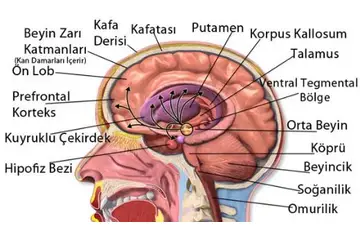

Beyinde kitle ameliyatı, genellikle tümörler, kist veya diğer anormal oluşumların cerrahi olarak çıkarılması amacıyla yapılan bir işlemdir. Bu tür bir ameliyat, beyin dokusuna doğrudan müdahale gerektiği için belirli riskler taşır ve sonrasında hastalar için çeşitli zorluklar ortaya çıkabilir. İşte bu makalede, beyin kitle ameliyatının riskleri ve sonrası hakkında detaylı bir inceleme yapılacaktır. 1. Beyin Kitle Ameliyatının Riskleri Beyin kitle ameliyatı, birçok risk barındırır. Bu riskler arasında şunlar bulunmaktadır: